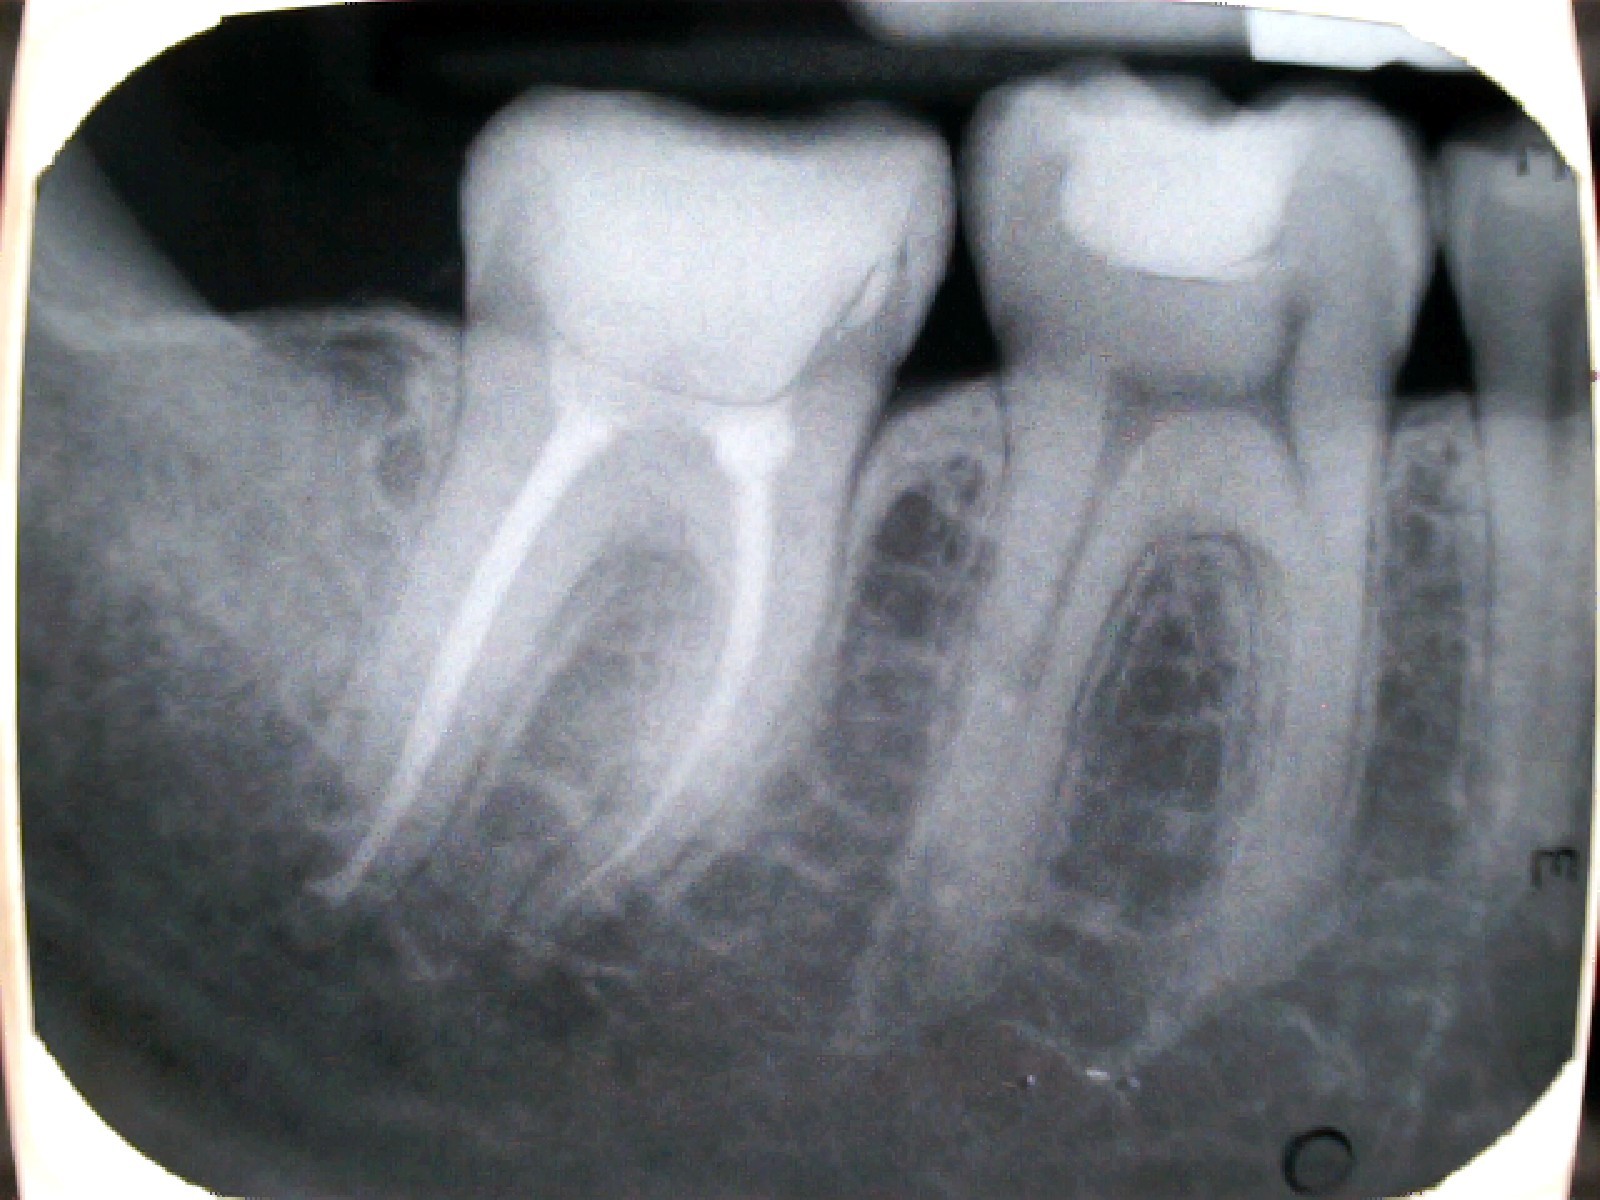

Álút képződés

Perforáció (fenti kép)

Túltömés

Alultömés

Lépcsőképződés

Tű-törése (fent)

Feltáratlan gyökércsatorna (fent)

Rosszul záró/nagy kiterjedésű tömés